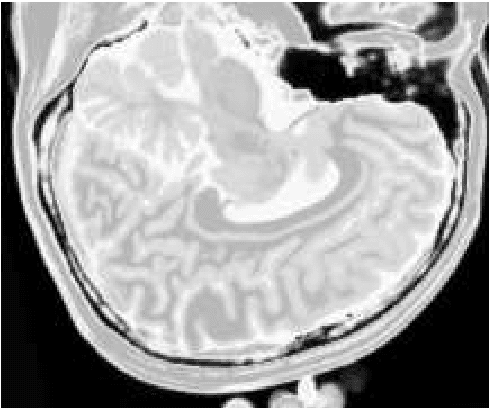

Abstract:Alzheimer's disease is the most common cause of dementia, yet difficult to accurately diagnose without the use of invasive techniques, particularly at the beginning of the disease. This work addresses the classification and analysis of multispectral synthetic images composed by diffusion-weighted magnetic resonance brain volumes for evaluation of the area of cerebrospinal fluid and its correlation with the progression of Alzheimer's disease. A 1.5 T MR imaging system was used to acquire all the images presented. The classification methods are based on multilayer perceptrons and classifiers of radial basis function networks. It is assumed that the classes of interest can be separated by hyperquadrics. A polynomial network of degree 2 is used to classify the original volumes, generating a ground-truth volume. The classification results are used to improve the usual analysis by the map of apparent diffusion coefficients.

Abstract:Multispectral image analysis is a relatively promising field of research with applications in several areas, such as medical imaging and satellite monitoring. A considerable number of current methods of analysis are based on parametric statistics. Alternatively, some methods in Computational Intelligence are inspired by biology and other sciences. Here we claim that Philosophy can be also considered as a source of inspiration. This work proposes the Objective Dialectical Method (ODM): a method for classification based on the Philosophy of Praxis. ODM is instrumental in assembling evolvable mathematical tools to analyze multispectral images. In the case study described in this paper, multispectral images are composed of diffusion-weighted (DW) magnetic resonance (MR) images. The results are compared to ground-truth images produced by polynomial networks using a morphological similarity index. The classification results are used to improve the usual analysis of the apparent diffusion coefficient map. Such results proved that gray and white matter can be distinguished in DW-MR multispectral analysis and, consequently, DW-MR images can also be used to furnish anatomical information.

Abstract:The unsupervised classification has a very important role in the analysis of multispectral images, given its ability to assist the extraction of a priori knowledge of images. Algorithms like k-means and fuzzy c-means has long been used in this task. Computational Intelligence has proven to be an important field to assist in building classifiers optimized according to the quality of the grouping of classes and the evaluation of the quality of vector quantization. Several studies have shown that Philosophy, especially the Dialectical Method, has served as an important inspiration for the construction of new computational methods. This paper presents an evaluation of four methods based on the Dialectics: the Objective Dialectical Classifier and the Dialectical Optimization Method adapted to build a version of k-means with optimal quality indices; each of them is presented in two versions: a canonical version and another version obtained by applying the Principle of Maximum Entropy. These methods were compared to k-means, fuzzy c-means and Kohonen's self-organizing maps. The results showed that the methods based on Dialectics are robust to noise, and quantization can achieve results as good as those obtained with the Kohonen map, considered an optimal quantizer.

Abstract:The materialist dialectical method is a philosophical investigative method to analyze aspects of reality. These aspects are viewed as complex processes composed by basic units named poles, which interact with each other. Dialectics has experienced considerable progress in the 19th century, with Hegel's dialectics and, in the 20th century, with the works of Marx, Engels, and Gramsci, in Philosophy and Economics. The movement of poles through their contradictions is viewed as a dynamic process with intertwined phases of evolution and revolutionary crisis. In order to build a computational process based on dialectics, the interaction between poles can be modeled using fuzzy membership functions. Based on this assumption, we introduce the Objective Dialectical Classifier (ODC), a non-supervised map for classification based on materialist dialectics and designed as an extension of fuzzy c-means classifier. As a case study, we used ODC to classify 181 magnetic resonance synthetic multispectral images composed by proton density, $T_1$- and $T_2$-weighted synthetic brain images. Comparing ODC to k-means, fuzzy c-means, and Kohonen's self-organized maps, concerning with image fidelity indexes as estimatives of quantization distortion, we proved that ODC can reach almost the same quantization performance as optimal non-supervised classifiers like Kohonen's self-organized maps.

Abstract:Alzheimer's disease is the most common cause of dementia, yet hard to diagnose precisely without invasive techniques, particularly at the onset of the disease. This work approaches image analysis and classification of synthetic multispectral images composed by diffusion-weighted magnetic resonance (MR) cerebral images for the evaluation of cerebrospinal fluid area and measuring the advance of Alzheimer's disease. A clinical 1.5 T MR imaging system was used to acquire all images presented. The classification methods are based on multilayer perceptrons and Kohonen Self-Organized Map classifiers. We assume the classes of interest can be separated by hyperquadrics. Therefore, a 2-degree polynomial network is used to classify the original image, generating the ground truth image. The classification results are used to improve the usual analysis of the apparent diffusion coefficient map.